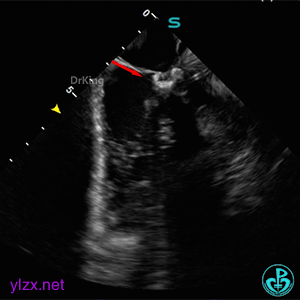

ICE下多切面观察封堵器形态及瓣膜活动状况

封堵器骑跨于室间隔两侧,周围瓣膜正常摆动。

锁定封堵器后观察位置形态

锁定后可见位置形态完好,盘面平整,扣合良好,无周围瓣膜影响。